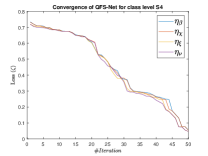

The suitable tailoring of the phase angle in the Hadamard gate advocates the stability of the QFS-Net or its convergence which is very crucial for self-supervised networks where the loss function (here error function) is dependent on the interconnection weights. Hence, the phase angles are evaluated using and as given in Equations 18 and 21, respectively. It is worth noting that the qutrit based quantum neural network provides faster convergence compared to the classical neural networks. This is due to the fact that whereas the classical neural networks are formed using the multiplication of input vector and the weight vector guided by an activation function, the quantum-based networks incorporate the frequency components of the weights and their inputs thereby enabling faster convergence of the network states. This inherent novel feature of the quantum neural networks facilitates the qutrit based fully self-organized quantum algorithm to be employed in QFS-Net to converge super-linearly, as shown in Figure 3. The loss function cum QFS-Net network error function is defined on quantum measurement in the following way.

where, represents the true interconnection weight terms of the inter-connection weights as expressed using the Hadamard gate () at an instance (). is a coherent error function of and . Convergence analysis of the proposed qutrit-inspired QFS-Net is provided in Appendix Section -A and demonstrated experimentally with qubit embedded QIS-Net [39] as shown in Figure 3. It can be summarized that the convergence of the QFS-Net is faster than that of the QIS-Net and also follows super-linearity. This claim is also substantiated by the number of iterations required to converge for each image slice in QFS-Net and QIS-Net as illustrated in Figure 4.